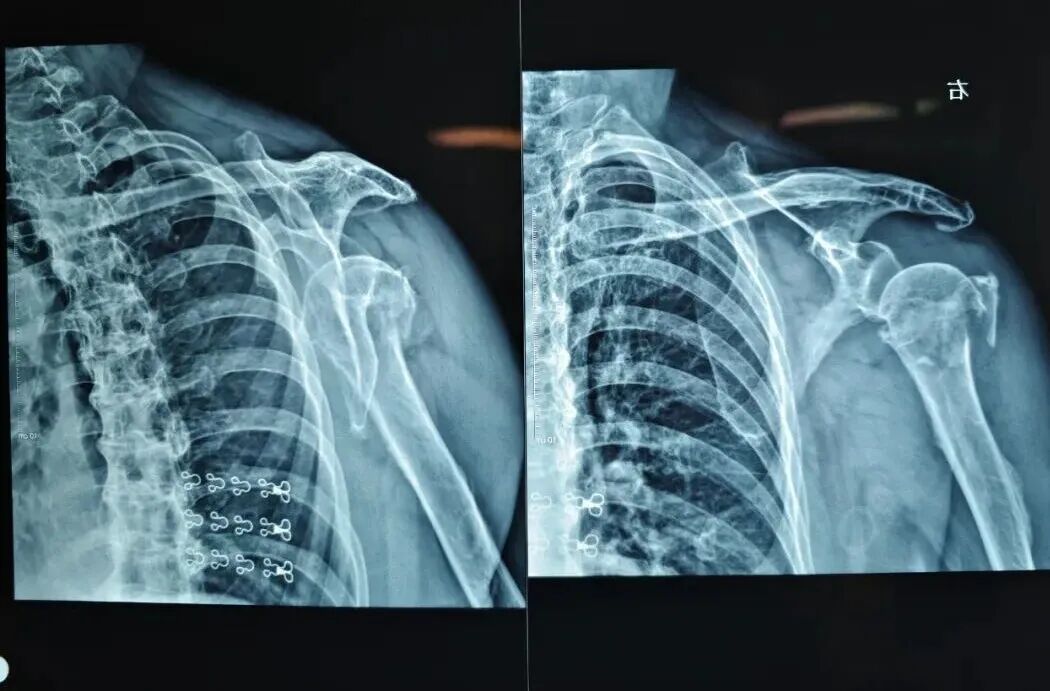

图片

图4 解剖髓内支撑重建系统示意图

刘国辉主任介绍,老年性骨质疏松病人的肱骨近端粉碎性骨折一直是困扰临床医生的一大难题。该系统核心理念是通过髓内支撑+解剖重建,恢复肱骨近端的生理力学稳定性。这一系统在解决高龄骨质疏松肱骨近端骨折中,能够有效避免传统钢板固定失败的风险,已逐渐在全国推广。作为全国多中心临床研究协作单位,我科在该系统的推广和临床验证中承担了重要角色。此次成功实施湖北省首例“解剖髓内支撑重建系统”手术,是我科不断创新、追求卓越的又一里程碑。